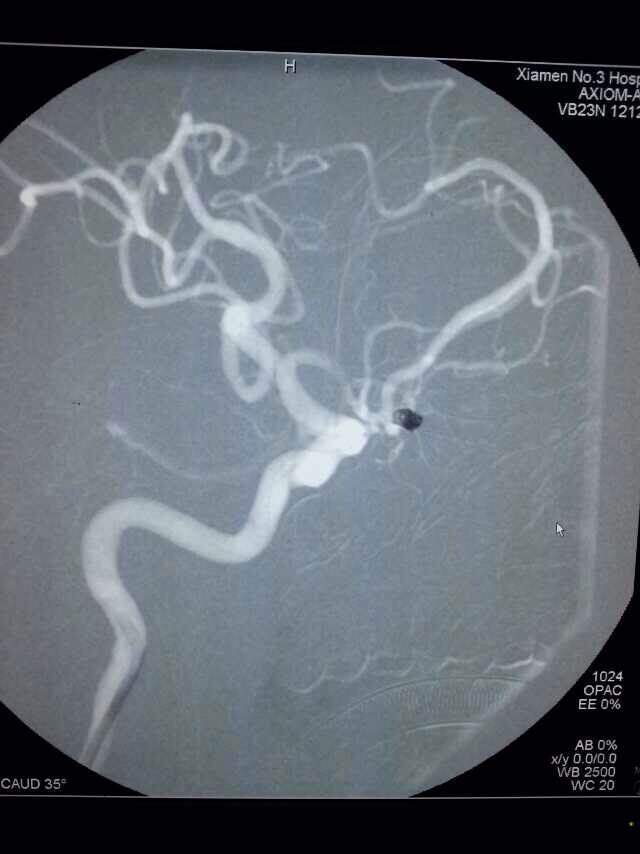

2014520是个特别的日子,第三医院手术室灯火通明,神经外科调集所有的技术团队手术一台接一台,有脑动脉瘤破裂的,有脑外伤出血的,忙碌不停。